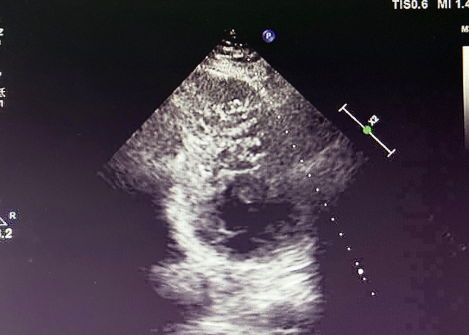

入院后,患者接受超聲心動圖檢查,結(jié)果顯示左心室心肌呈典型 “海綿樣” 改變,可見多發(fā)、粗大的肌小梁和深陷的隱窩,非致密化心肌層與致密化心肌層比值(NC/C)>2.3,完全符合左心室心肌致密化不全(LVNC)的超聲診斷標(biāo)準(zhǔn)。

LVNC 的超聲表現(xiàn)

(1)特征性表現(xiàn)左心室壁明顯增厚,內(nèi)層心肌呈 “網(wǎng)狀” 疏松結(jié)構(gòu),外層致密心肌變薄,血流灌注顯示隱窩內(nèi)血流緩慢,這種情況容易形成血栓。(2)診斷標(biāo)準(zhǔn)(Jenni 標(biāo)準(zhǔn))收縮末期非致密化心肌層與致密層厚度比 > 2,可見深陷的肌小梁間隱窩與心室腔交通。